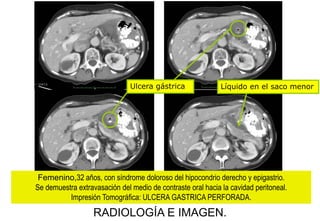

Ulcera gástrica

Líquido en el saco menor

Femenino,32 años, con síndrome doloroso del hipocondrio derecho y epigastrio.

Se demuestra extravasación del medio de contraste oral hacia la cavidad peritoneal.

Impresión Tomográfica: ULCERA GASTRICA PERFORADA.